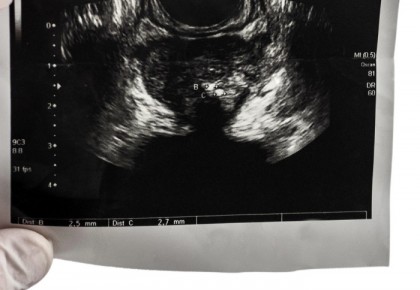

Noul studiu a analizat utilizarea scanării cu ultrasunete multiparametrice (mpUSS), care implică utilizarea unei sonde pentru a realiza imaginile prostatei. Dispozitivul este plasat în rect È™i emite unde sonore care sunt apoi transformate în imagini ale organelor. Medicul care efectuează testul foloseÈ™te, de asemenea, tipuri speciale de imagistică cu ultrasunete care analizează cât de rigid este È›esutul È™i cât de alimentat cu sânge este un È›esut. DeÈ™i mpUSS este mai disponibil pe scară largă decât mpMRI, nu au existat studii la scară largă care să îi valideze eficacitatea pentru detectarea cazurilor de cancer de prostată.

foto: Imperial College London